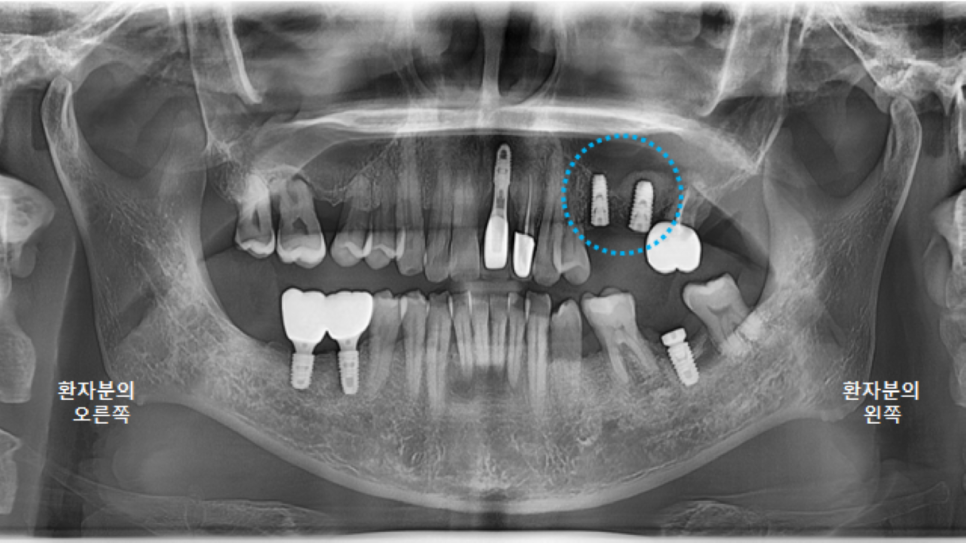

전체적인 구강 판단을 위해

파노라마 엑스레이 사진을 찍었습니다.

왼쪽 큰앞니도 빠져있지만,

오른쪽위 큰어금니, 오른쪽 아래 큰어금니도 발치된 상태였고,

왼쪽 위 브릿지 상태도 좋지는 않았습니다.

왼쪽 아래 큰어금니 하나는 뿌리만 남은 상태였어요.